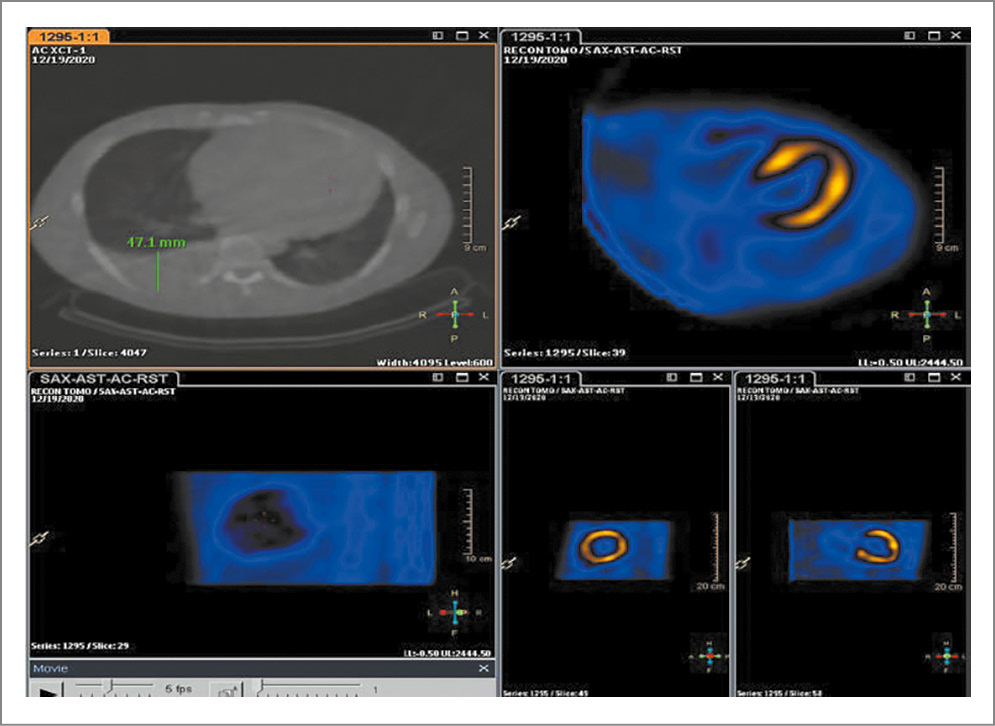

Следующей целью после подтверждения диагноза амилоидоза является его типирование. От этого зависит дальнейшее назначение специфической терапии, схемы которой кардинально различаются у AL- (химиотерапия) и TTR-амилоидоза (селективный стабилизатор транстиретина). Одним из важных исследований, позволяющих типировать амилоидоз, является сцинтиграфия миокарда с 99mTc – пирофосфатом технеция. В рамках исследования оценивается накопление радиоизотопов (РФП) в миокарде относительно костной ткани, на основании чего оценивается степень накопления РФП: 2 и 3-я степени (grade 2, grade 3) с высокой вероятностью указывают на TTR-амилоидоз [8].

По результатам исследования данного пациента: на сцинтиграммах, выполненных в 3 стандартных проекциях, костные структуры не визуализируются. Определяется интенсивное тотальное накопление РФП в миокарде ЛЖ и правого желудочка. Соотношение накопления РФП в миокарде относительно накопления в контрлатеральной зоне 2,5 (соотношение больше, чем 1,5, характерно для ATTR-амилоидоза); рис. 4. При оценке сцинтиграмм в режиме однофотонной эмиссионной компьютерной томографии (ОЭКТ) визуализируется интенсивное накопление РФП во всем миокарде ЛЖ, в том числе в проекции папиллярных мышц (признак гипертрофии ЛЖ), grade 3 (рис. 5).

Рис. 5. Сцинтиграммы в режиме ОЭКТ